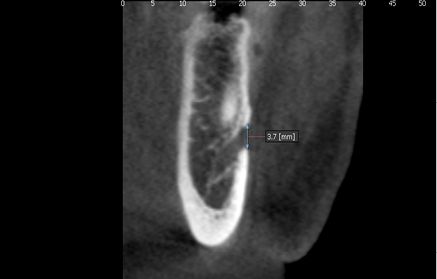

The distances from the upper and lower cortical areas of the mental foramen to the alveolar crest and the mandibular basal bone respectively were analyzed, as well as the size of the hole on the transaxial cut. There we considered the distance between the upper and lower cortical areas of the structure, and the measurements were classified into ranges (Figures 1 and 2).

Fig. 2: Size of mental foramen

The distances from the upper and lower cortical areas of the mental foramen to the alveolar crest and the mandibular basal bone respectively were analyzed, as well as the size of the hole on the transaxial cut. There we considered the distance between the upper and lower cortical areas of the structure, and the measurements were classified into ranges (Figures 1 and 2).

Fig. 2: Size of mental foramen